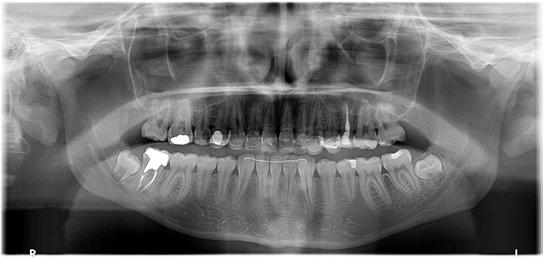

Figure 1. Example of characteristic Wickham striae and reticular pattern on buccal mucosa used to clinically diagnose OLL and OLP cases. Erythematous areas also seen. Figure 2. Frequency and percent of study patients using specific medications with color-coded drug classes.

Results

A total of 162 patients were identified who were diagnosed with OLL/OLP and/or treated in the NYU College of Dentistry Oral Medicine Clinic from Jan. 1, 2015, through Sept. 30, 2019. Sub jects were predominantly female, with 109 females (67%) and 53 males (33%). The average age was 59.5 years, with a range of 26 to 88 years. About 30% of patients fell within the ages of 60 to 69 years. Among all subjects, 46.9% (n=76) were found to have biopsy-proven diagnoses of OLP or OLL.

The most common medication taken among subjects was metformin, comprising 24.6% (n=40). The most common phar macologic class was statin medications, at 36.4% (n=59); specifi cally, 15% (n=25) of patients took atorvastatin and 9% (n=15) took simvastatin. We also discovered that 17.9% (n=29) took proton-pump inhibitors and, interestingly, 16.7% (n=27) took le vothyroxine. These results are summarized in Figure 2 and Table 1.

Antihypertensives were the most common therapeutic class of medications among our subjects, at 49.4% (n = 80). As seen in Fig ures 2 and 3, when hypertension medications (color-coded green) are further subdivided into pharmacologic classes, beta blockers were the most associated with OLL/OLP, followed closely by angiotensinII-receptor blockers (ARBs) and calcium channel blockers (CCB). The thiazides are the next frequent type of hypertension medications taken by our OLL/OLP patient cohort. To our knowledge, our study is the first to further subtype the large and diverse class of hyperten sion medications associated with oral lichenoid lesions.